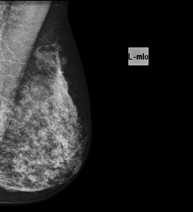

Digital mammography

Digital mammography is an innovative breast examination technique that uses a low radiation dose, thus reducing exposure compared to conventional mammography. The image is digitised using special cassettes on a system known as CR (Computed Radiography). These digitalisation techniques provide excellent images, especially in breasts that are difficult to examine, such as glandular breasts, which appear dense on mammograms, enabling better detection of tumours in this group of patients.